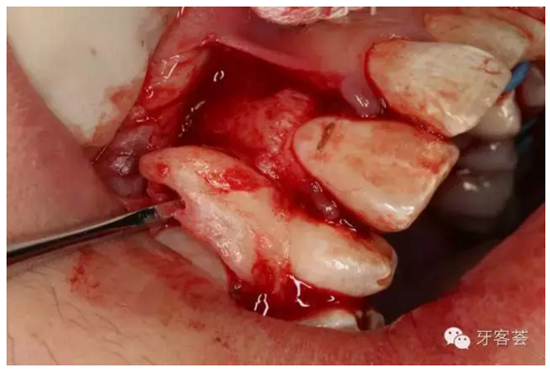

圖6:切開(kāi)、翻瓣、暴露13牙冠。